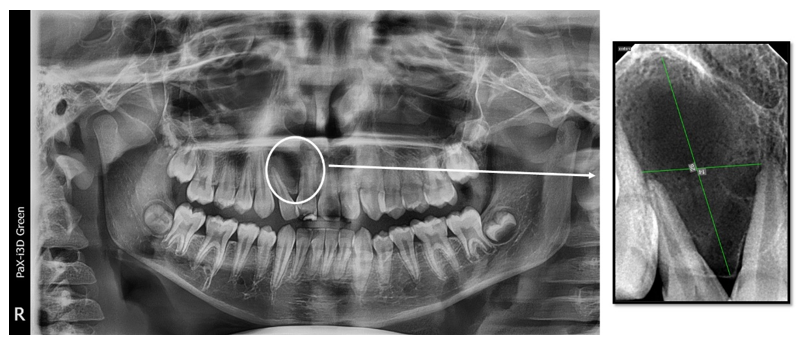

A 13‐year‐old male child had a chief complaint of a severely mesially displaced upper right lateral incisor (#12), which made his parents seek orthodontic treatment (Figure 1). The child was referred from the Department of Orthodontics to the Department of Endodontics for periapical surgery before the orthodontic treatment. The patient had no significant medical problems, and the upper right central incisor # 11 had a Class IV composite restoration. A cold vitality test with an ice stick showed no response in central #11 and lateral incisors # 12.

Figure 1 Pre-operative clinical photos showing lateral view. (A) and occlusal view (B) of a tilted lateral right incisor (tooth #12) (arrow).